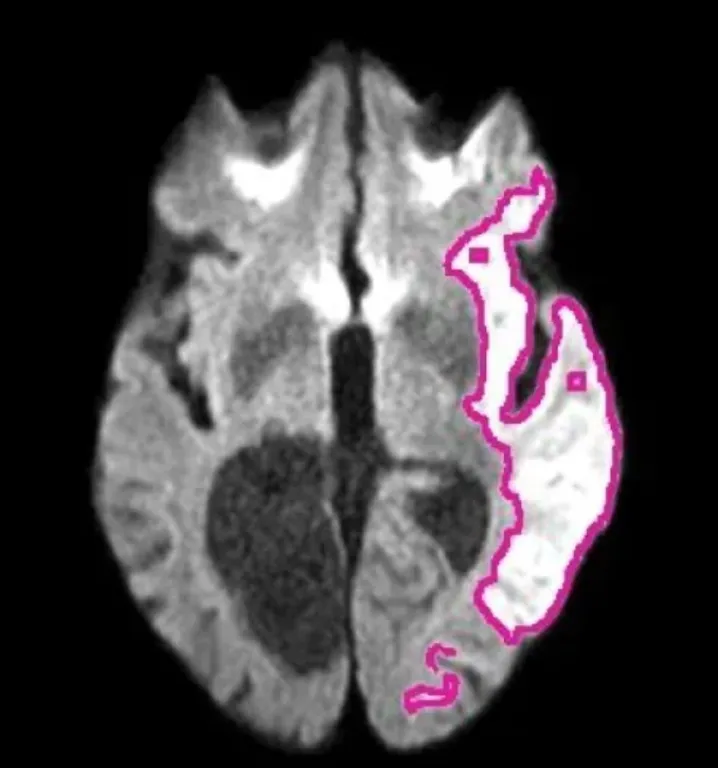

DeepISLES se basa en Inteligencia Artificial (IA) y fue validado en el exigente desafío internacional ISLES’22, así como en imágenes de resonancia magnética provenientes de distintos hospitales del mundo. Logró mejoras de hasta +7,4 % en el índice Dice y +12,6 % en el F1-score frente a métodos previos, manteniendo su rendimiento incluso con imágenes, lesiones y pacientes muy diversos.

Uno de los hitos del desarrollo fue un “pseudo Turing test”: expertos en neurorradiología recibieron imágenes con lesiones delineadas automáticamente por DeepISLES y otras hechas manualmente por colegas, sin informarles cuáles eran de cada origen. El resultado sorprendió: los especialistas prefirieron en mayor medida las segmentaciones generadas por el algoritmo que las realizadas por otros expertos humanos.

El sistema, disponible en código abierto, puede integrarse en hospitales y centros de diagnóstico para analizar resonancias de forma casi instantánea, señalando con precisión la zona del cerebro afectada por la falta de irrigación. En la práctica, esto podría acortar drásticamente los tiempos de diagnóstico en guardias y ayudar a estandarizar la calidad de atención en todo el mundo.